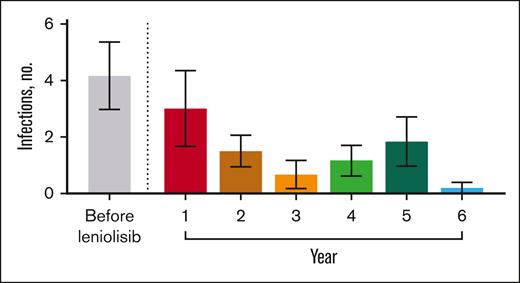

Before receiving leniolisib, all patients had difficulty fighting infections (Table 3). While receiving leniolisib, the number or severity of infections decreased for all, from a mean of 3 in year 1 to 0.2 in year 6 (Figure 2).

Number of infections over time. Mean number of infections before and throughout exposure to leniolisib. n values for before leniolisib and years 1, 2, 3, 4, 5, and 6 are as follows: 6, 6, 6, 6, 6, 6, and 5, respectively. “Before leniolisib” comprises multiple years of recurrent/unresolved infection history. Post-leniolisib exposure includes only acute infections. Dotted line separates infections that occurred before and during treatment with leniolisib. Error bars are ± standard error of the mean.

Number of infections over time. Mean number of infections before and throughout exposure to leniolisib. n values for before leniolisib and years 1, 2, 3, 4, 5, and 6 are as follows: 6, 6, 6, 6, 6, 6, and 5, respectively. “Before leniolisib” comprises multiple years of recurrent/unresolved infection history. Post-leniolisib exposure includes only acute infections. Dotted line separates infections that occurred before and during treatment with leniolisib. Error bars are ± standard error of the mean.